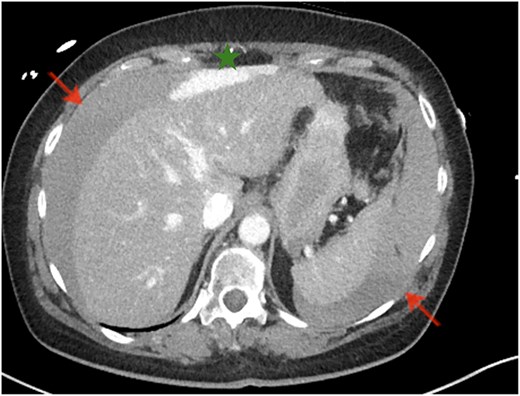

Subsequently, due to a noticeable drop in hemoglobin (Fig. 1) and significant abdominal distention prompted an eFAST ultrasound, which revealed free fluid around the liver. A contrast-enhanced computed tomography (CT) scan of the thorax and abdomen demonstrated a central and peripheral pulmonary artery embolism with a massive thrombus burden, as well as extensive free fluid in all abdominal quadrants. Fresh blood adjacent to the ventral margin of the left liver lobe indicated parenchymal damage and capsular injury (Fig. 2). An emergency laparotomy confirmed a laceration of the left liver lobe, which was repaired using Vicryl 0 sutures and TachoSil. Postoperatively, an interventional thrombectomy of the pulmonary circulation was performed.

CT of the abdomen. Significant amounts of free fluid in all quadrants (arrows), with fresh blood adjacent to the ventral edge of the left liver lobe (star).